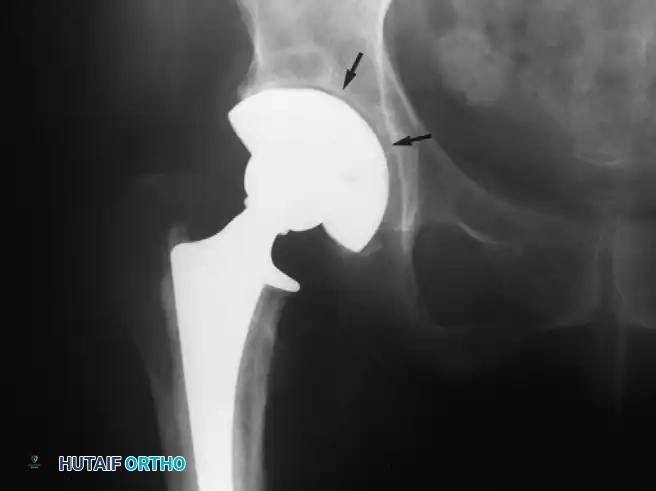

Center of Rotation and Joint Reaction Forces

The superior-inferior and medial-lateral location of the hip's center of rotation profoundly affects the forces generated around the implant. Mathematical models by Johnston, Brand, and Crowninshield demonstrated that the joint reaction force is minimized when the hip center is restored to its true anatomical location.

Conversely, placing the hip center in a superior, lateral, or posterior position significantly increases joint reaction forces and abductor fatigue. While isolated superior displacement (without lateralization) produces only relatively small increases in periacetabular stress—a technique sometimes necessary in developmental dysplasia of the hip (DDH) or severe revision scenarios with deficient superior bone stock—clinical studies consistently document a higher incidence of progressive radiolucencies and component migration when the hip center is left in a nonanatomical position.